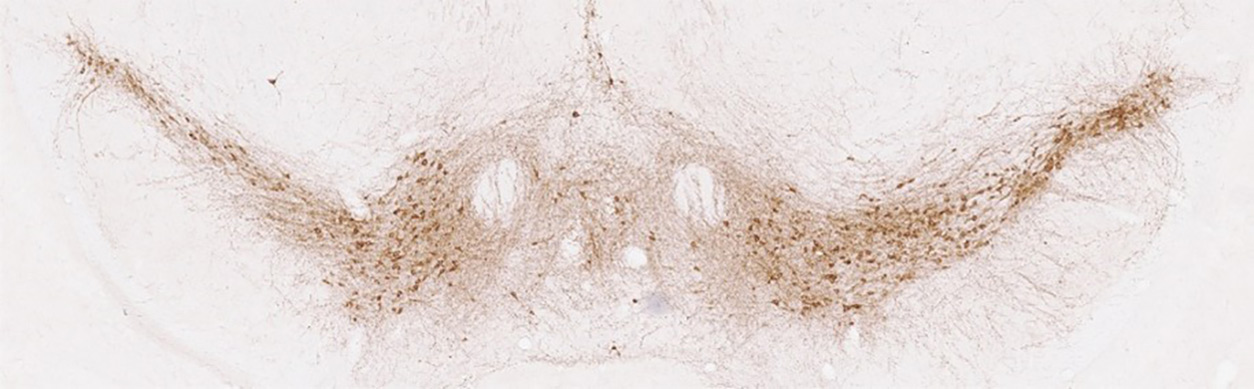

Parkinson’s disease results from the degeneration of neurons in the brain that produce the chemical messenger dopamine. This degeneration leads to various symptoms, including slowed movement, problems with speech or balance, and tremors in the limbs and face. Though the exact cause of Parkinson’s disease remains unknown, Cui’s research group is working to understand how energy-producing organelles in cells called mitochondria might play a role.

Cui: During my postdoctoral training at the National Institute on Alcohol Abuse and Alcoholism [NIAAA], I worked on dopamine-producing neurons. These neurons are associated with two main types of conditions: drug addiction and Parkinson’s disease. While most of my time at NIAAA was dedicated to addiction research, NIEHS provided a great opportunity to study Parkinson’s, as the disease has been strongly linked to environmental factors, such as pesticides and heavy metals.